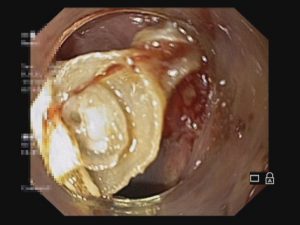

BVXA – VƯỢT QUA CƠN NGUY KỊCH NHỜ CAN THIỆP NỘI SOI MẬT TỤY NGƯỢC DÒNG KỊP THỜI

Ngày 10/10/20, Trung tâm Nội soi tại BVXA đã tiến hành can thiệp nội soi mật – tụy ngược dòng (ERCP) cấp cứu bệnh nhân V.T. (58 tuổi, ngụ tại Huyện Củ Chi, TP.HCM) bị nhiễm trùng đường mật nặng kèm viêm tụy cấp do sỏi ống mật chủ. Nhờ sự nhanh nhạy, can thiệp kịp thời của các bác sĩ mà bệnh nhân đã vượt qua cơn nguy kịch.